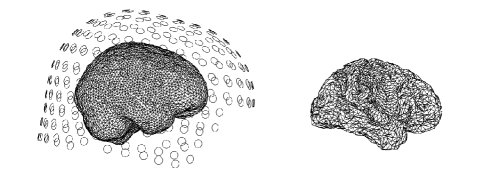

Covariance matrices representing functional connectivity can be computed from the signals arising from functional imaging modalities. The choice of a specific functional imaging modality is generally driven by the preference to have high spatial resolution signals, and thus high spatial resolution covariance matrices, versus high temporal resolution, and thus the possibility to study the temporal dynamic of the covariance matrices. Functional Magnetic Resonance falls in the first category, while Electroencephalogram (EEG) and Magnetoencephalography (MEG) in the second. However, high temporal resolution does generally come at the price of indirect measurements and, as shown in Figure 1 in the case of MEG data, the signals are in practice detected on the sensors space. It is however of interest to produce results on the associated signals on the cerebral cortex, which we will refer to as brain space. The signals on the brain space are functional images whose domain is the geometric representation of the brain and are associated with the neuronal activity on the cerebral cortex. We borrow here the notion of brain space and sensors space from Johnstone and Silverman (1990) and we use it throughout the paper for convenience, however it is important to highlight that the formulation of the problem is much more general than the setting of this specific application.

The signals on the brain space are related to the signals on the sensors space by a forward operator, derived from the physical modeling of the electrical/magnetic propagation, from the cerebral cortex to the sensors. This is generally referred to as the forward problem. For soft-field methods like EEG, MEG and Functional Near-Infrared Spectroscopy (Mosher et al., 1999; Eggebrecht et al., 2014; Ferrari and Quaresima, 2012; Singh et al., 2014; Ye et al., 2009), the forward operator is defined through the solution to a partial differential equation of diffusion type. Such a mapping induces a strong degree of smoothing and consequently the corresponding inverse problem, i.e. the reconstruction of a signal on the brain space from observations in the sensors space, is strongly ill-posed. In fact, signals with fairly different intensities on the brain space, due to the diffusion effect, result in signals with similar intensities in the sensors space. In Figure 1, we show an example of a signal on the brain space and the associated signal on the sensors space.

We now introduce the problem using our driving application as an example. To this purpose, let a be a closed smooth two-dimensional manifold embedded in , which in our application represents the geometry of the cerebral cortex. An example of such a surface is shown on the top right of Figure 1. We denote with the space of square integrable functions on . Define to be a random function with values in a Hilbert functional space with mean , finite second moment, and assume the continuity and square integrability of its covariance function . The associated covariance operator is defined as , for all . Mercer’s Lemma (Riesz and Szokefalvi-Nagy, 1955) guarantees the existence of a non-increasing sequence of eigenvalues of and an orthonormal sequence of corresponding eigenfunctions , such that

In the case of single subject studies, the surface is the subject’s reconstructed cortical surface, an example of which is shown on the right panel of Figure 1. In this case, it is natural to assume that there is one common forward operator for all the detected signals. In the more general case of multi-subject studies, is assumed to be a template cortical surface. We are thus assuming that the individual cortical surfaces have been registered to the template , which means that there is a smooth and one-to-one correspondence between the points on each individual brain surface and the template surface , where the PC functions are defined.

By segmentation of the 3D structural MRI, it is possible to separate gray matter from white matter, in order to extract the cerebral cortex structure. Subsequently a mid-thickness surface, interpolating the mid-points of the cerebral cortex, can be estimated, resulting in a 2D surface embedded in a 3D space that represents the geometry of the cerebral cortex. In practice, such a surface, sometimes referred to as cortical surface, is a triangulated surface. Moreover, from the 3D structural MRI, a surface describing the individuals’ head can be extracted. The latter plays a role in the derivation of the model for the electrical/magnetic propagation of the signal from the cerebral cortex to the sensors. An example of the cortical surface of a single subject, is shown on the right panel in Figure 1, instead the associated head surface and MEG sensors positions are shown on the left panel of the same figure.